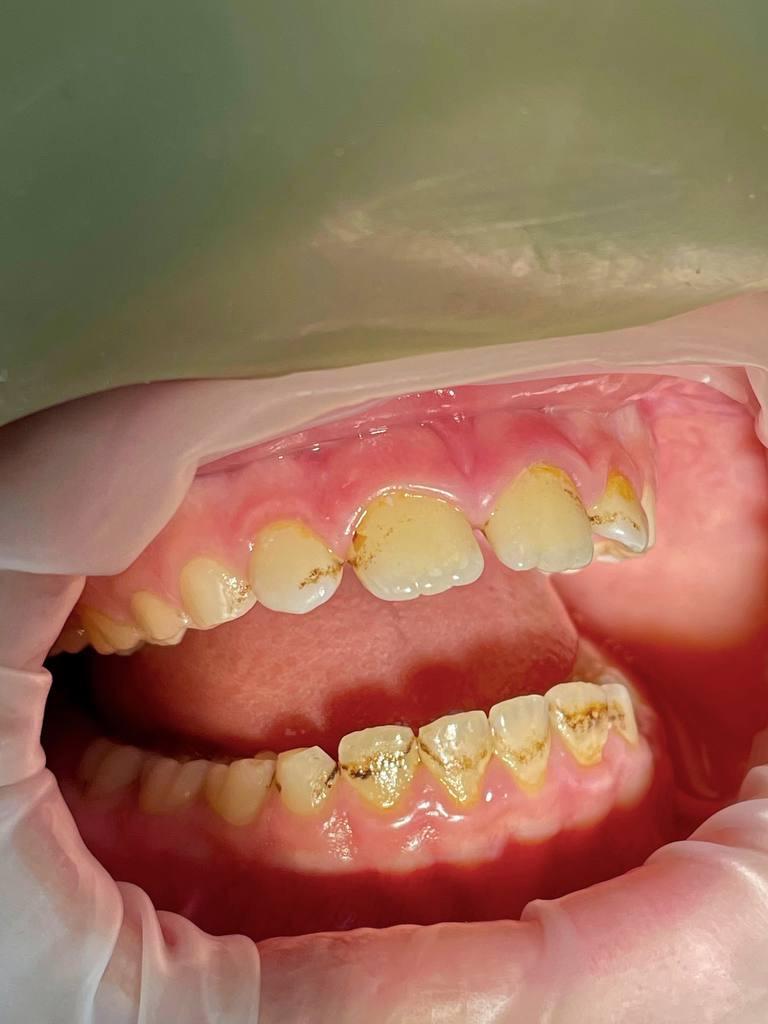

ДО: Заметны налет, пигментация и твердые зубные отложения, что придает неухоженный вид зубам.

После: Поверхность зубов очищена, восстановлен их естественный цвет, отсутствуют твердые зубные отложения и налет. Зубы выглядят здоровыми и ухоженными, а десны - свежими и более розовыми.